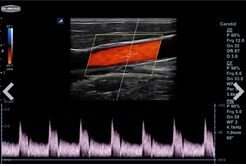

경동맥협착증검사는초음파를 이용한 검사가가장 안전하고 정확합니다.

경동맥초음파검사는목부위에서 뇌로 이어진혈관인 경동맥의 좁아진정도나

혈류가 제대로가는지를 확인하는 검사입니다.

초음파를이용하기 때문에 환자에게고통이나 불편감을 일으키지않는 안전한 검사입니다.

특히경동맥의 동맥경화정도를 측정하여

심장혈관이나 뇌혈관등에서 동맥경화를예측하고 미리 예방하는데매우 도움이 됩니다.

경동맥초음파검사는가볍게 어지러움을 느끼는경우뿐만 아니라

뇌졸증및 심혈관질환으로 치료받은가족력이 있는 경우,

당뇨나고혈압 고지혈증의 각종성인병이 있는 경우에특히 필요합니다.